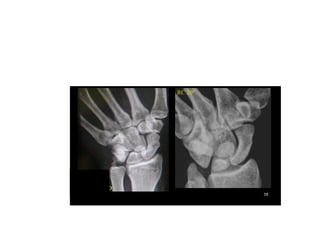

INCIDÊNCIAS PUNHO E MÃO

Osso escafoide

Maior abertura e visualização ossos

do carpo região ulnar